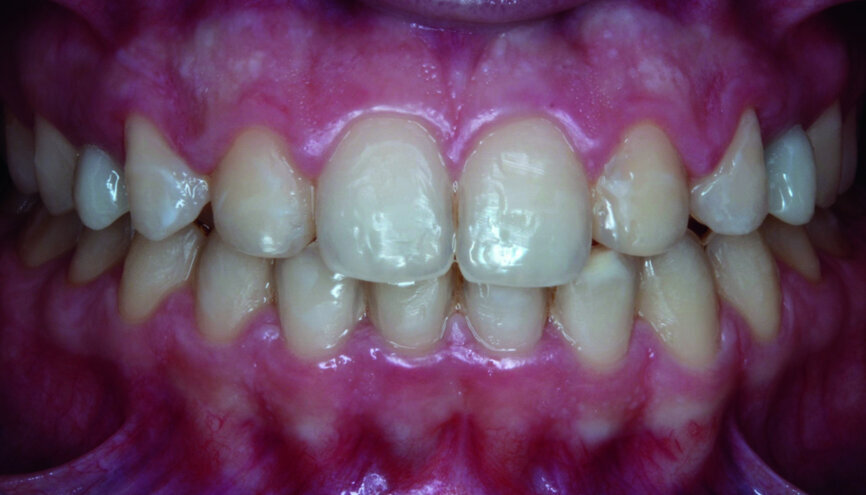

At the end of orthodontic treatment, gingival margins were well aligned, midlines were centred and canines and first premolars were positioned to facilitate the restorative phase of treatment (Figs. 34–36). At this phase, a final CR mounting and wax-up was performed (Figs. 37–39), as well as the anterior teeth restorations (Fig. 40).

Orthodontic treatment has improved both dental and facial aesthetics (Figs. 41–47) and the functionality of the occlusion (Figs. 48–52).